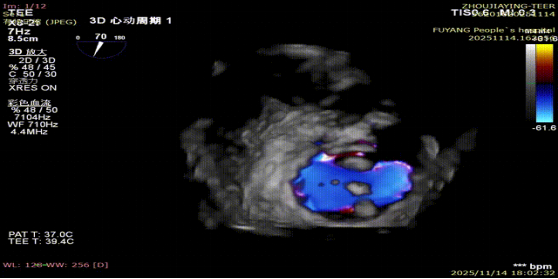

手术当日,在全身麻醉及TEE全程导航下,陈玺全副主任团队凭借丰富的临床经验与精湛操作技巧,顺利完成房间隔穿刺、瓣叶精准定位等关键步骤。针对患者二尖瓣A2/P2 区域反流靶点,团队精准夹合瓣叶,经X-plane技术与三维超声反复确认夹持质量后,成功释放一枚MitraClip XTR夹子。术后即时评估显示,患者二尖瓣反流由术前3 +重度降至轻度,平均跨瓣压仅3mmHg,手术达到预期效果,全程无并发症发生。

术前MR反流